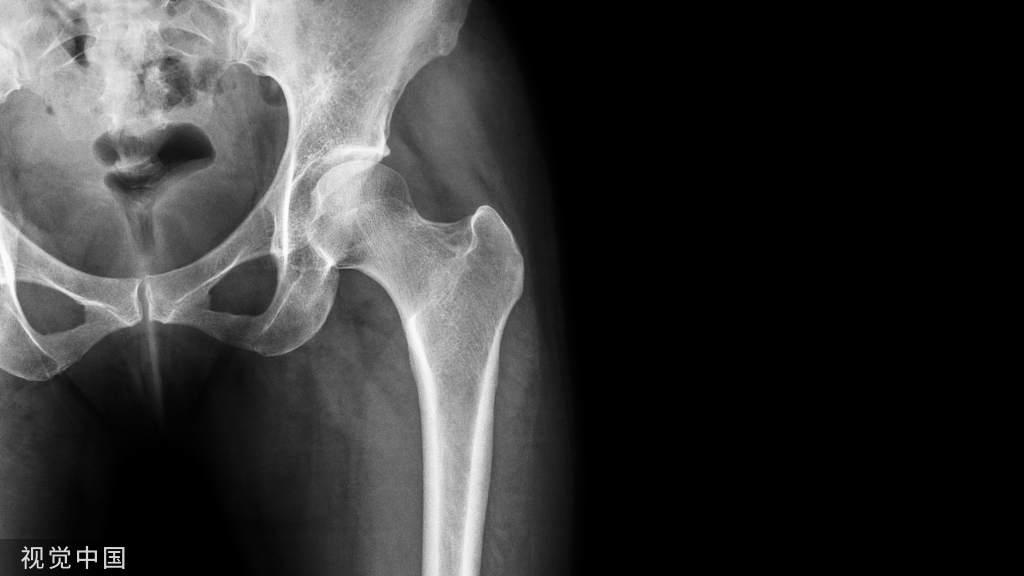

胫骨后外侧平台骨折的复位与固定一直是困扰骨科医生的难题,仅依靠前外侧入路较难对后外侧平台形成有效支撑,通常需侧卧或俯卧位,将内植物直接置入后外侧。对后外侧平台的复位固定,主要包括采用低切迹的内植物经前外侧置入截骨入路(股骨外侧髁截骨或腓骨头截骨)直接将内植物置入骨折后方两种方法